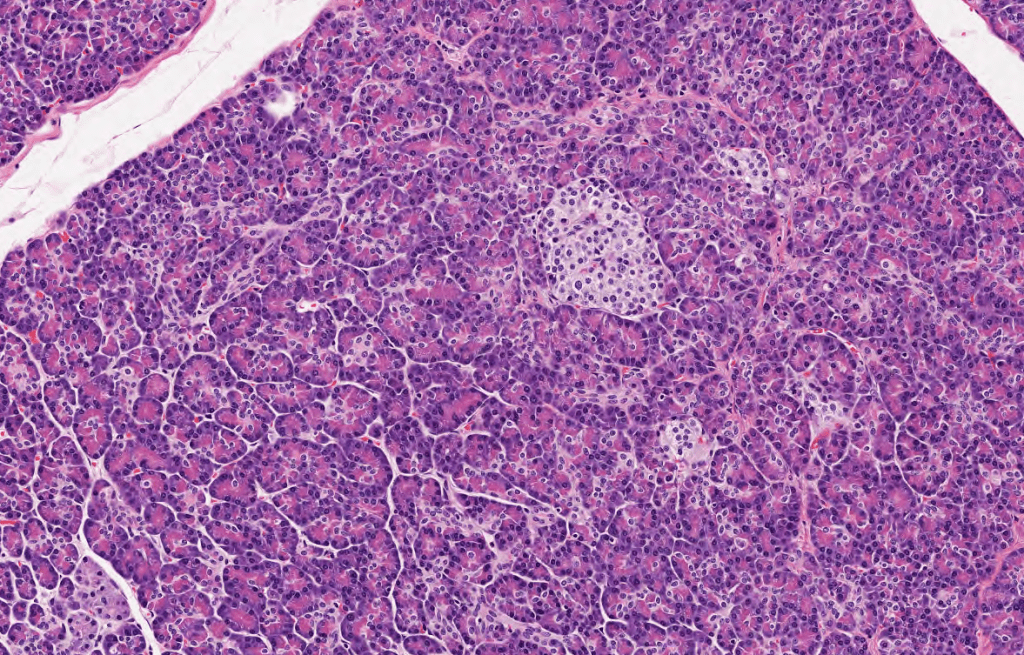

PÁNCREAS

Los acinos pancreáticos forman una parte esencial del estroma del páncreas.Identifique el Islote de Langerhans en el medio de la imagen, sus células sueles presentarse pálidas al HyE.La Cromogranina A es un marcador neuroendocrino que nos permite visualizar fácilmente los islotes de Langerhans.La basofilia basal y la acidofilia apical son características que siempre nos ayudan a identificar acinos pancreáticos.Con técnica de fluorescencia podemos identificar las células alfa (rojo) y las células beta (verde) del páncreas.Identifique la acidofilia apical y la basofilia basal de los acinos pancreáticos. Recuperada de ATLAS FacMed UNAM.El páncreas exocrino es regulado por CCK y Secretina.El páncreas endocrino consta de células alfa, beta y delta.Páncreas, HyE.Las células de los islotes expresan Cromogranina A.Diferencias entre basofilia y acidofilia en el acino pancreático.La secreción de los acinos pancreáticos es de tipo serosa, son altamente basófilos y tienen gránulos de zimógenos.Los zimógenos del páncreas son enzimas digestivas inactivas.Con una técnica coloidal podemos identificar la enorme vascularización del páncreas.La estrella mostrada señala un islote de Langerhans, tinción de Azán.Técnica de Grimelius (izq.) y Aldehído-fuscina (der.)